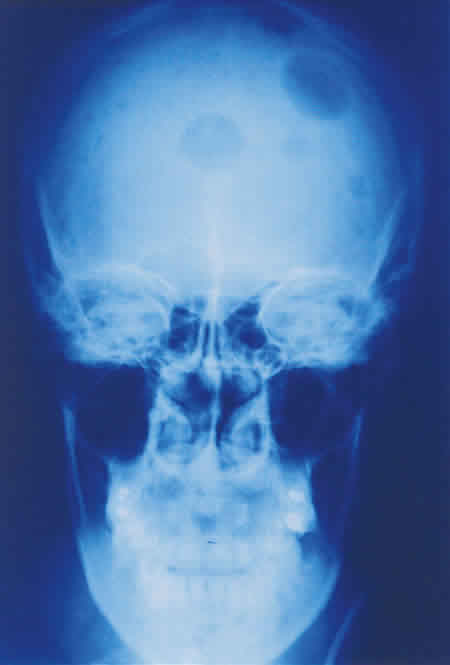

Fig. 5: Radiografía simple: imágenes osteolíticas en cráneo.